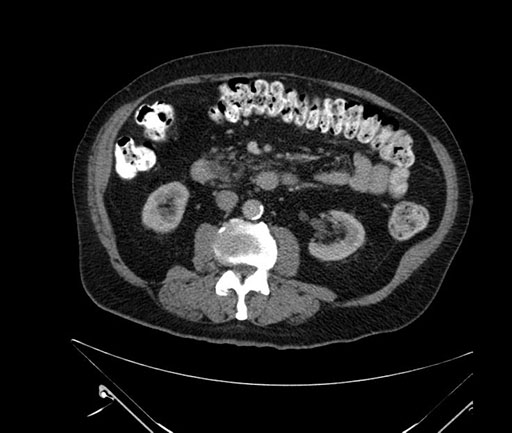

Imaging Analysis

Look through the patient's CT scan to identify any areas of concern for the necessary procedure.

Based on your CT findings, which issue(s) would give reason for "planned slowing down moment(s)" in this case?